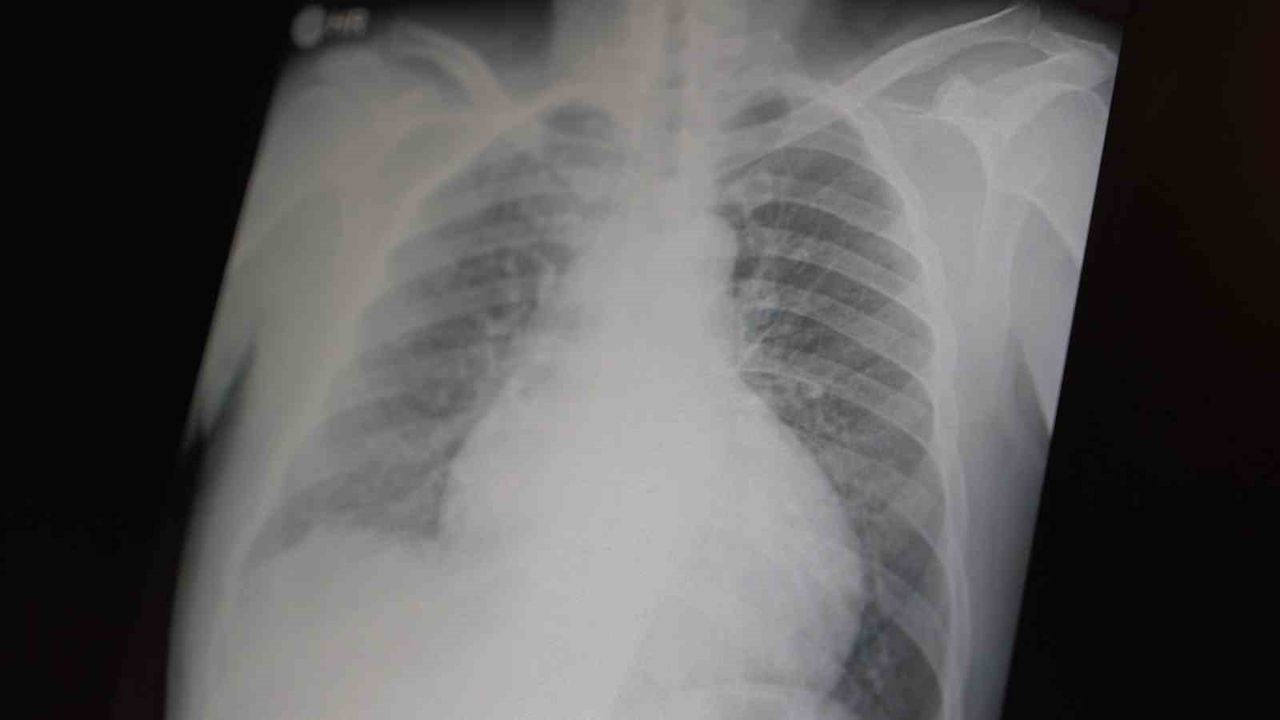

Prof. Dr. Şevket Özkaya, çocukları ve gençleri etkileyen bağımlılıklar hakkında açıklamalarda bulundu. Metamfetaminin sentetik bir yasaklı madde olduğunu ve kullanımının ölümcül sonuçlar doğurduğunu ifade eden Özkaya, 'Tüm dünyada çocukları ve gençleri etkileyen iki önemli bağımlılıktan bahsetmek istiyorum. Bunlar metamfetamin ve kokain bağımlılığıdır. Metamfetamin en ölümcül, en çok bağımlılık yapan, okul çağında en kolay ulaşılabilen bir sentetik yasaklı maddedir . Kullanıma bağlı ciddi akciğer ve karaciğer sorunları ortaya çıkıyor. Çok küçük dozlarda bile anında bağımlılık yapabiliyor ve tedaviyle bırakılması çok zor bir bağımlılıktır' dedi.

Açıklamalarında, her iki yasaklı madde beyin hasarı oluşturduğunu ve nöro sinir hücrelerini harap ederek solunum ve kalbin durmasına sebep olduğunu vurgulayan Özkaya, 'Metamfetamin tüm dünyada bir sorun olmanın ötesinde, ülkemizde de gençlerimizi etkileyen toplumsal bir sorun olarak görülmelidir' ifadelerini kullandı.